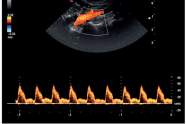

心脏解剖 M 型(CMM):

M 型取样线可 360 度任意旋转,并可同时设定 3 条自由角度取样线。同时显示 同一时相 3 条线上组织 M 型信息,实现在同一个心动周期中,在同一时相对不同的 心肌节段、瓣膜进行对比观察和测量分析。可应用于心脏和腹部探头(心脏功能评估)。

大鼠心脏

小鼠心脏